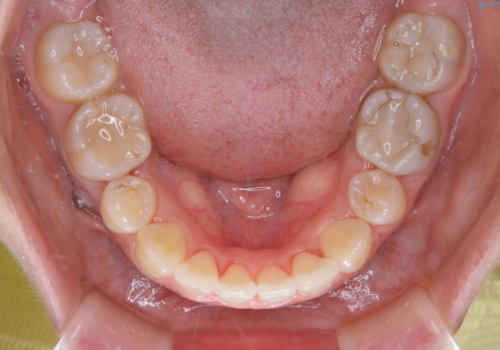

下の前歯にはかなり多くの歯石が付いており、デンタルフロスでもう少し防げるため、使用法や頻度を確認しました。

インビザラインの矯正治療は、マウスピースの使用時間が少ないとマウスピースと歯のフィッティングが悪くなりシュミレーション通りに歯が動かなくなるため、追加アライナーといって、再度スキャニングを行い新しいフィットの良いマウスピースに変えていきます。そのスキャニング時にアタッチメント(歯の表面に付いた突起)も除去するため、そのタイミングでクリーニングするのもおすすめです。